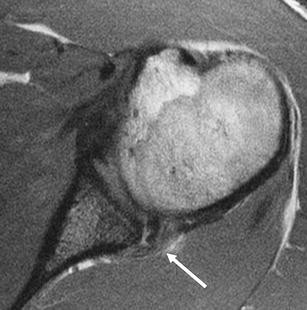

Fig. 2